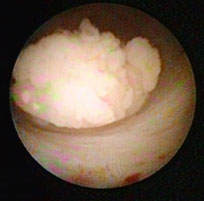

![]() Korallenförmiger, sogenannter papillärer Nierenbeckenkrebs |